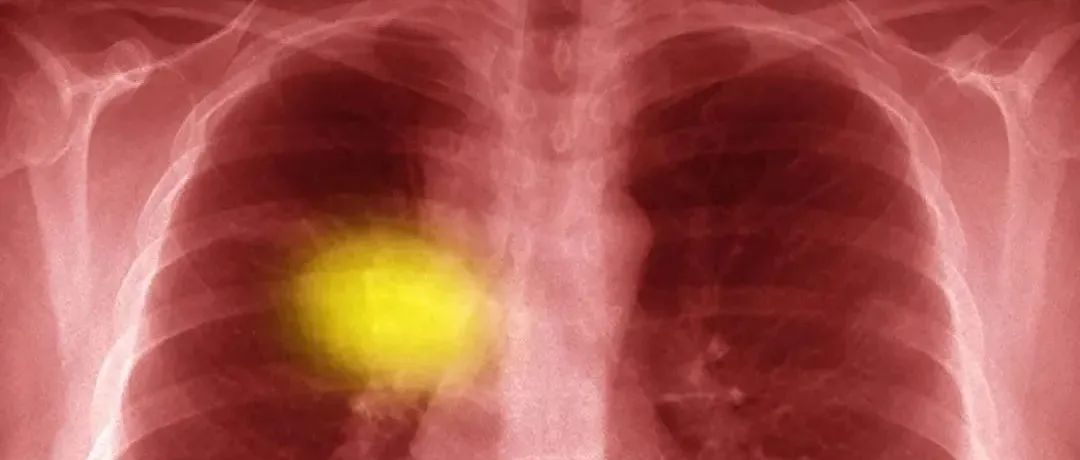

肺癌脊柱转移手术患者的生存预后分析

Edited by Spine Truth Editorial Team脊柱甘露语林®学术•疾病与健康科普•助学•公益行之2605天,第1580篇编译:张军 副主任医师   审校 总编辑:王海强 教授肺癌(lung cancer)具有侵袭性高、预后差的特点,是癌症导致死亡的主要原因之一。全球每年约有160万新发病例和140万死亡病例。骨是晚期肺癌最常见的转移部位之一,其中以脊柱转移最为常见,约30%-36%的肺癌患者发生脊柱转移。Karolinska等[1]研究表明,有骨转移和无骨转移的1年生存率分别为5%和37%。...